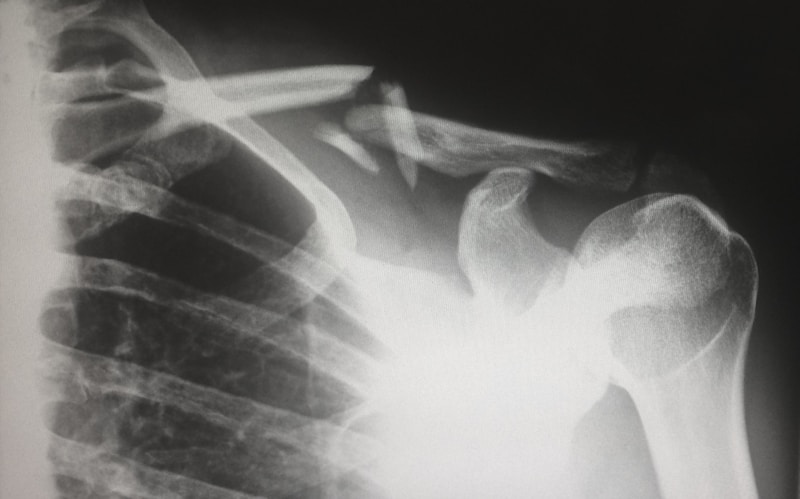

Radiografia de tórax com classificação OIT/ILO 2011 para diagnóstico precoce de pneumoconioses — silicose, asbestose, antracose. Leitura por médico B-reader certificado.

A classificação OIT 2011 gradua profusão, forma e extensão das opacidades. Cada categoria orienta aptidão, afastamento ou monitoramento.

Padrão internacional, categoria 0-3 + A/B/C

Classificação OIT revisada por dois B-readers independentes quando há discordância — padrão-ouro em pneumoconioses ocupacionais.